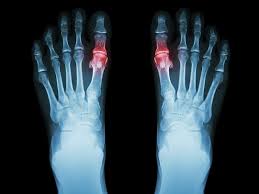

The Cartiva SCI is intended to treat painful arthritis in the joint of the big toe.

Tell your doctor if you have a form of arthritis called gout that also causes small lumps (tophi) to form under the skin around your joints. The Cartiva SCI might not work in your joint with this kind of arthritis.

• HOW HAVE WE TESTED THE CARTIVA SCI® IN CLINICAL TRIALS?

A controlled clinical study tested the Cartiva SCI. The study happened in hospitals in Canada and the United Kingdom. Patients had osteoarthritis in the joint of their big toe. Study patients received the Cartiva SCI or a fusion of their first joint. 202 patients were treated in this study. 152 patients received the Cartiva SCI implant. 50 patients had fusion surgery. Patients were seen over a two-year period from surgery including a visit two years after surgery. Of the Cartiva patients, 151 patients of the 152 were available for the two year visit and 47 of the 50 fusion patients were available at two years.

In the clinical study, 89% of Cartiva SCI patients had significant pain relief two years after treatment, while 98% maintained or improved their function at two years after treatment.

74% of patients maintained or improved their amount of motion at two years after treatment.